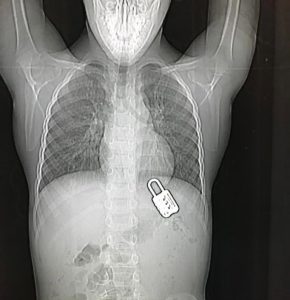

Hadassah Remove Padlock From Child’s Stomach

Tommy, a 6-year-old from Jerusalem, was admitted to Hadassah Hospital, Ein Kerem last week by his father after accidently swallowing a padlock.

They inserted a thread through Tommy’s mouth, knotted it around the padlock, and pulled it out sans surgery. “Tommy didn’t complain at all,” said Davidovics, “but we knew that is we didn’t get it out, it could tear his stomach, and cause him tremendous damage.”